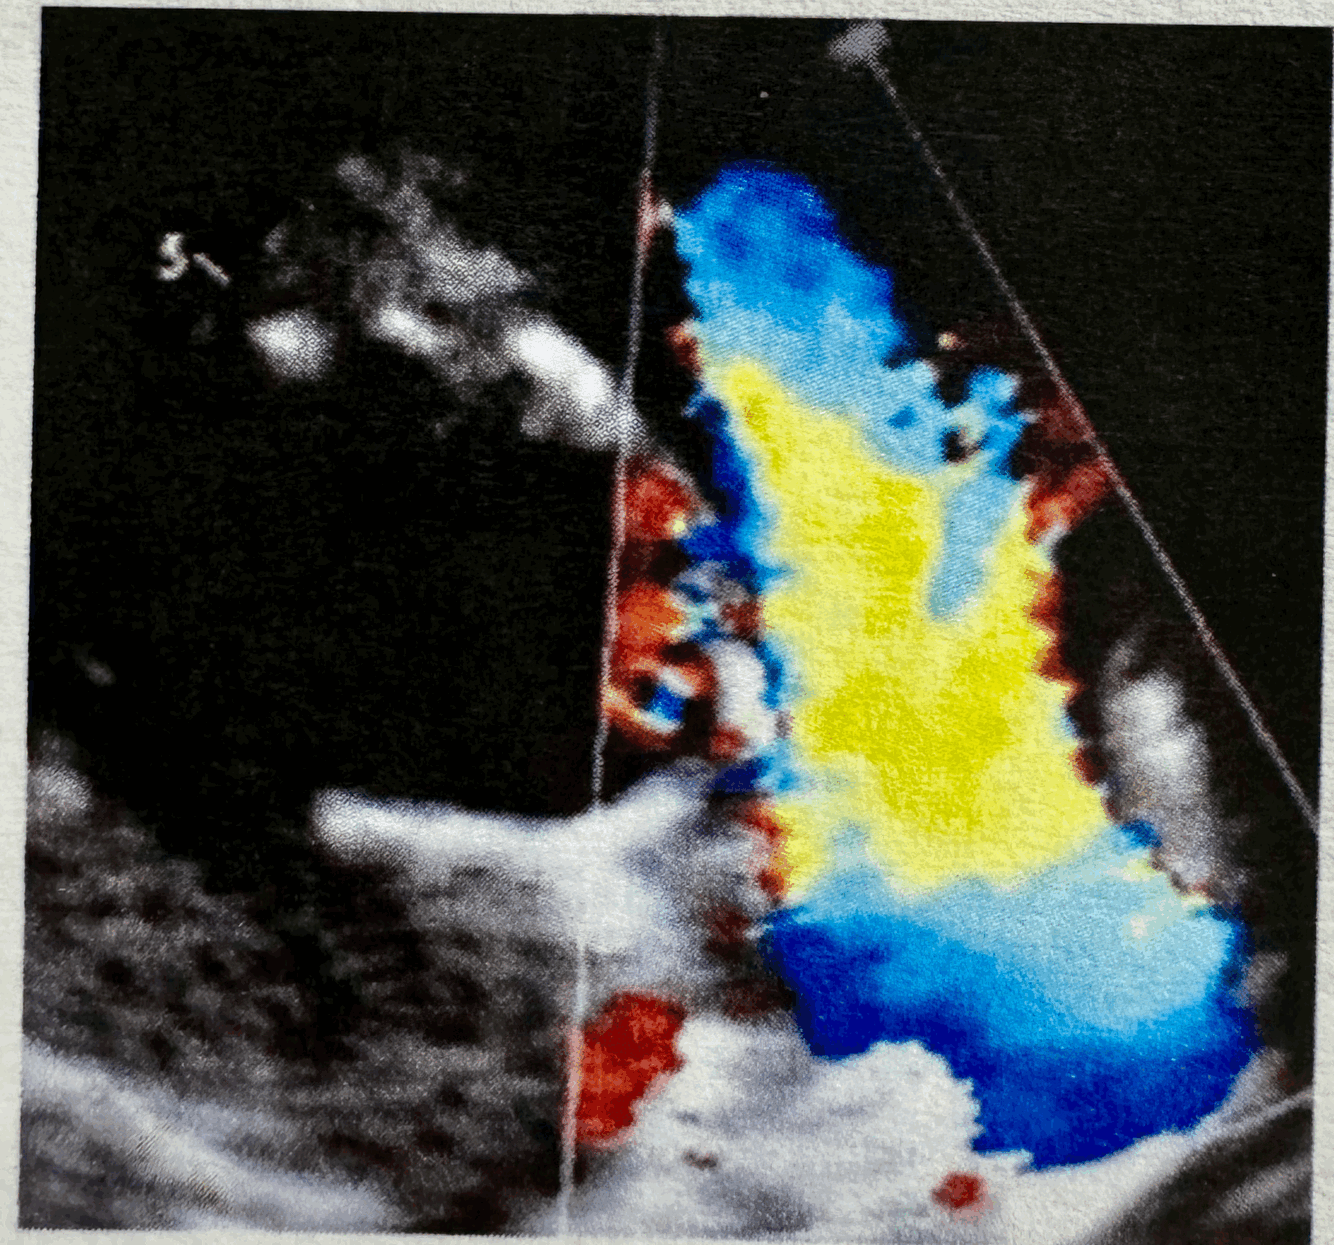

What Color Doppler is this of?

23

Q

24